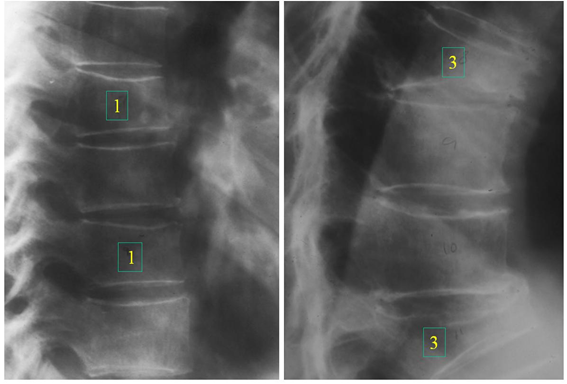

Due to the etiological complexity of back pain, it is common that an Osteoporotic fracture is not suspected and that it is often interpreted as muscle pain, such as a contracture. Another finding is the loss of height, which is usually gradual. The most frequent location of VF is in the middle region of the dorsal column T7 and T8 as well as in the dorsolumbar junction T12 - L1 as we see in Figure 2, Figure 3 and Figure 9 Many of these symptoms can become disabling. physically and psychologically due to its persistence, producing depression, social isolation and interpersonal relationship problems as well as difficulty falling asleep due to pain and depression, leading in severe cases to the loss of social identity.

Figure 2 Vertebral fractures at level T8 and T11, numbers 1 and 3 on the radiographs show the Genant classification: 1 mild and 3 severe.